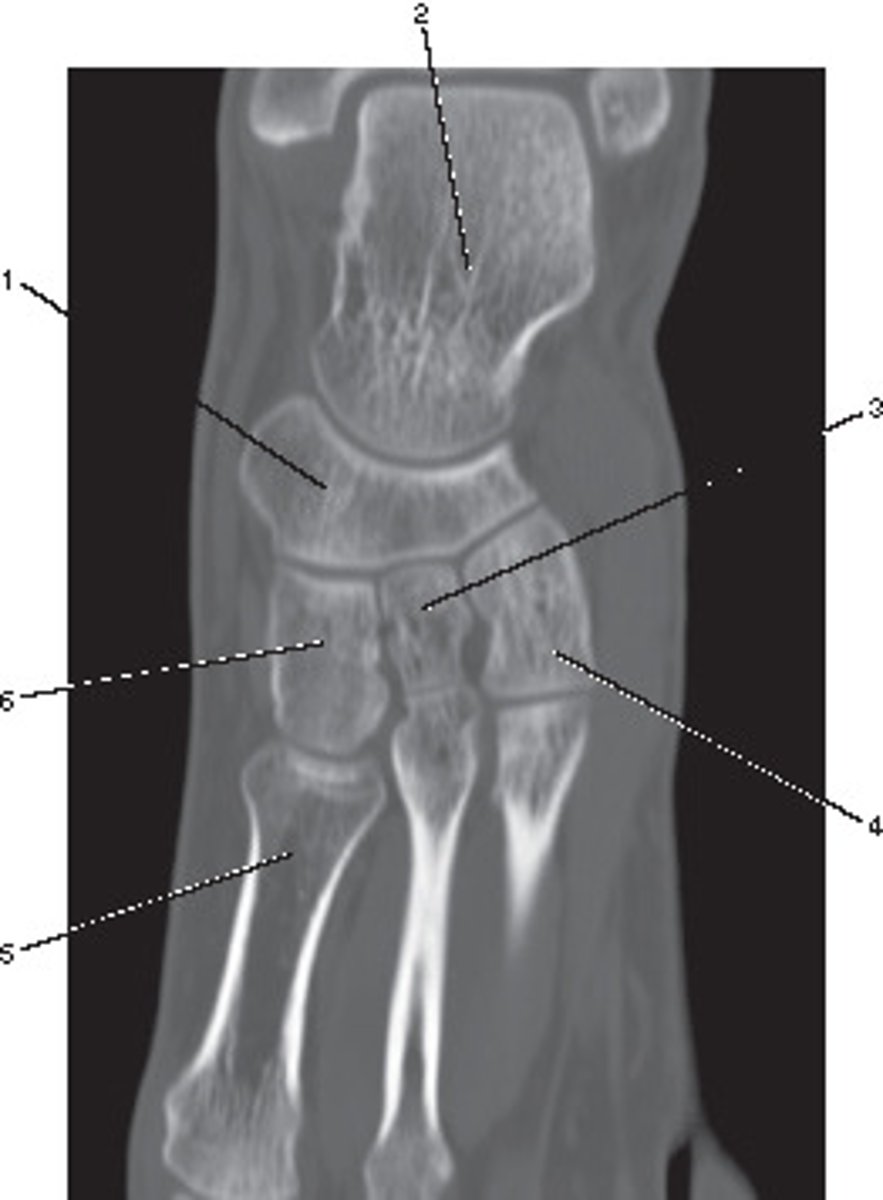

Fibula

Number 1 corresponds to which of the following?

<p>Number 1 corresponds to which of the following?</p>

Ulna

Number 5 corresponds to which of the following?

<p>Number 5 corresponds to which of the following?</p>